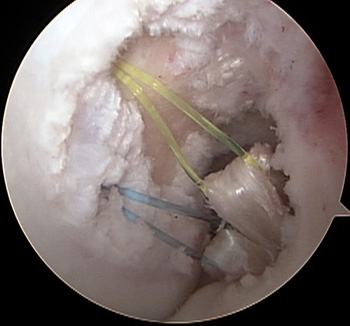

maestu1_fig6

Figura 6: vista artroscópica desde portal anterolateral de pasajes injertos en una rodilla izquierda.